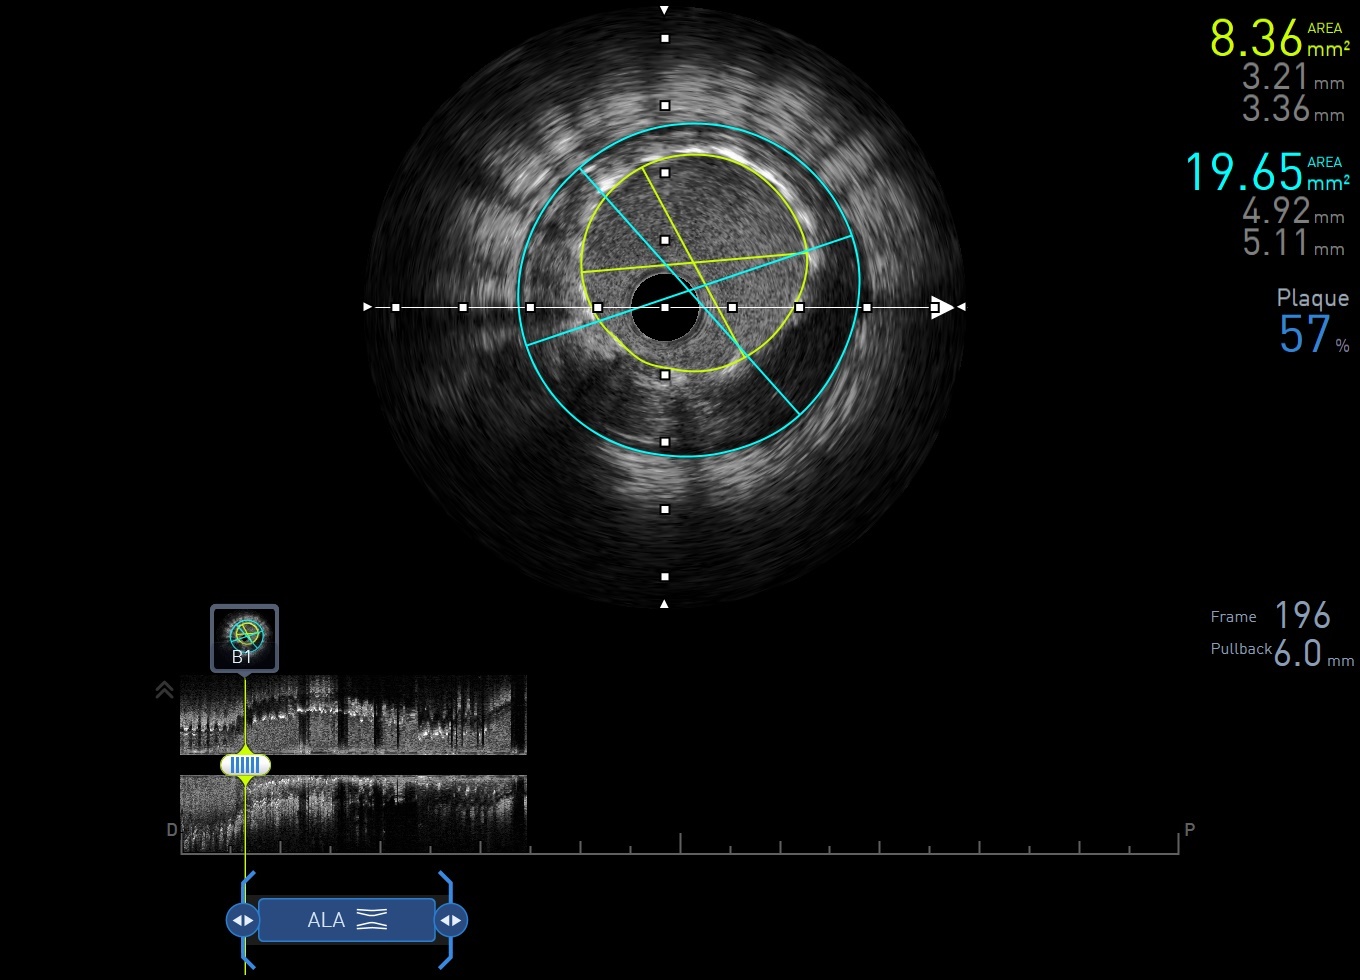

Catheterization found LAD-os CTO with collateral circulation from LCA and RCA. The largest collateral artery was originated from PL branch. Previous stent over RCA-m was found underexpanded with IVUS. Before proceeding to LAD CTO, we fixed underexpanded stent first with 4.0 x 12mm NC BC.

We did retrograde approach for LAD-os CTO. With Finecross microcatheter support, Sion Black was advanced to diagonal branch through PL branch. Then we engaged LCA with EBU 3.5 x 6 Fr GC and changed Sion Black to Fielder XTA. With Finecross support, Fielder XTA passed through LAD-os to diagonal CTO lesion and was advanced into LM, and it was confirmed by IVUS. Retrograde system was converted to antegrade with Tip-in technique, and antegrade microcatheter was advanced to diagonal branch. We then used IVUS to confirm the stump position of LAD-PMJ CTO. We once tried to use Crusade double lumen catheter and IVUS for stump wiring but 6 Fr GC was not large enough for using both devices simultaneously. We then marked the location of stump on angiogram, and tried to wire with Fielder XTA. Finally, Fielder XTA passed CTO stump with Finecross support, then we changed Fielder XTA to Gaia 1 and it was advanced to distal LAD. LAD CTO lesion was dilated with 1.0 and 2.0mm BC. IVUS showed that we were all the way in true lumen except a very short part in LAD-d. LAD-os to LAD-m lesion was scaffolded with 2.5 x 48mm DES and it was dilated with 3.0 x 12mm NC BC. For angiogram showed distal stent edge dissection and contrast leakage from second diagonal branch, we checked echocardiogram but found no pericardial effusion and vital signs were stable. Distal stent edge dissection was scaffolded with 2.5 x 12mm DES and LAD-d small vessel was dilated with 1.5mm BC. Final angiogram showed good result.